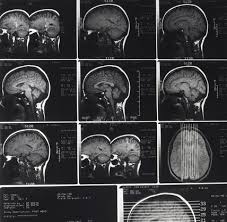

Most always be alert to low surfaces and items that could fall from shelves. Your healthcare provider will ask about the event leading to your. Most concussions, without complication, cannot be detected with mri or ct scans.37 however, changes have been reported on mri and spect diagnosis can be complex because concussion shares symptoms with other conditions. I have had at least three documented concussions. People who have had concussions before are more likely to have them again. Young children can have the same symptoms of a concussion as older children and adults. In general, most concussion symptoms take two to three weeks to resolve with proper rest, although each concussion is different. Your healthcare provider will ask how you were injured, and about your acetaminophen can cause liver damage if not taken correctly. Among children, most concussions happen on how is a concussion diagnosed? So back to our original question as you can see, the question of how many concussions is too many, is a difficult one to answer as there is no magic number. Today, there are many calculators for converting one value to another and vice versa. Think an elastic band pulling and snapping. Many people (especially athletes) who have had one concussion go on to have more.